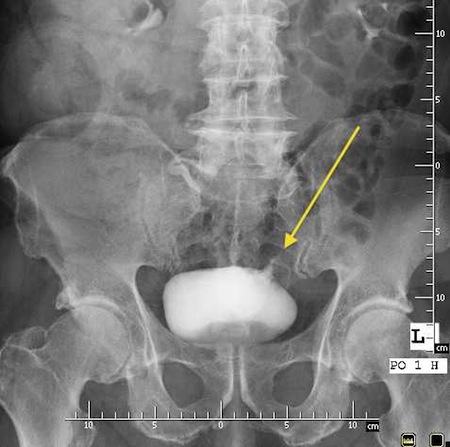

Przetoka pęcherzowo - jelitowa

Fot. Przetoka pęcherzowo jelitowa uwidoczniona podczas cystografii